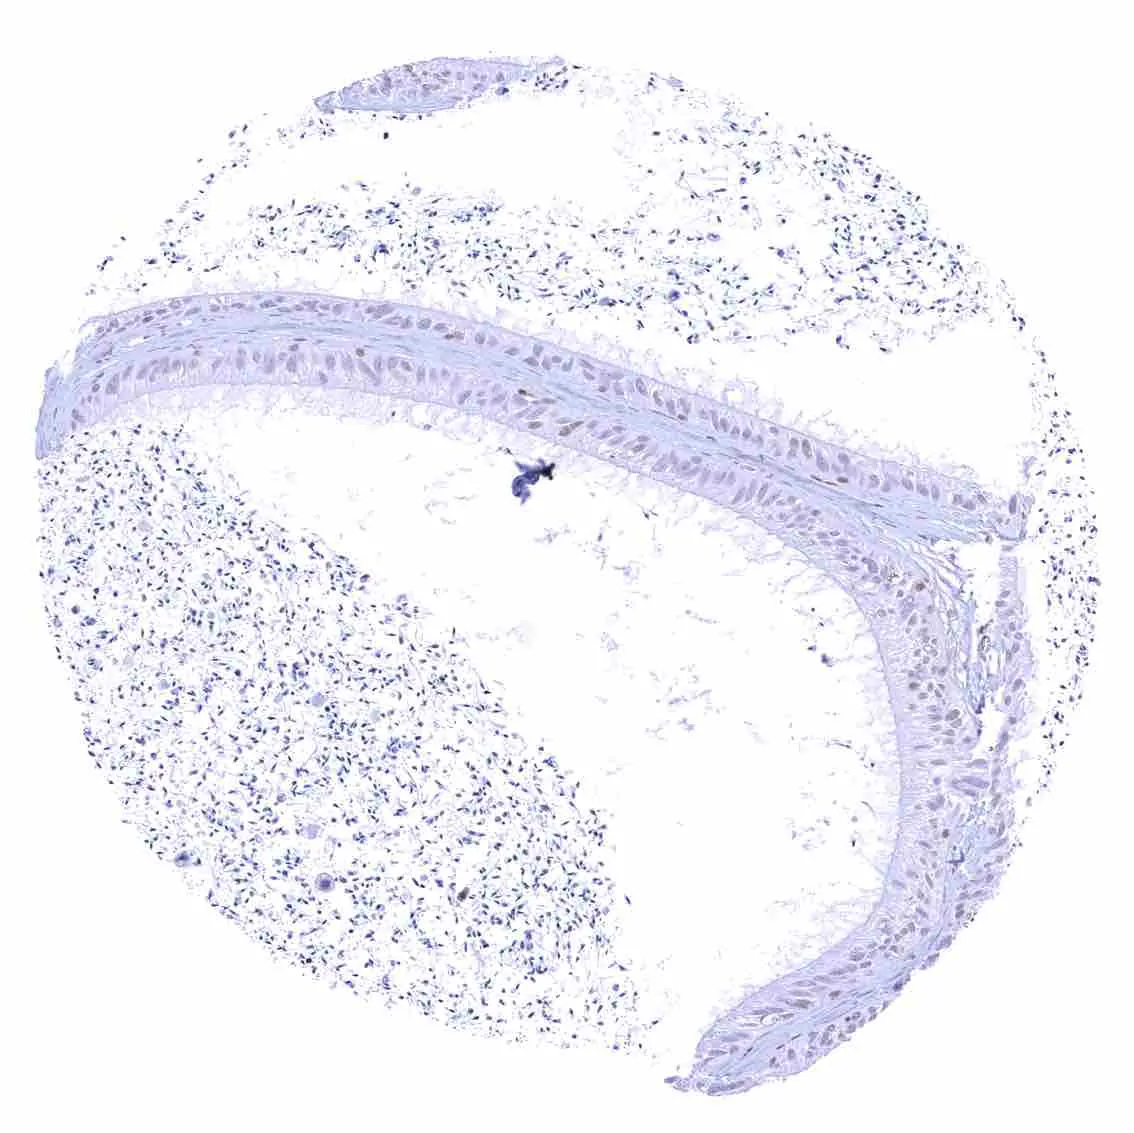

Esophagus, squamous epithelium – Nuclear staining of squamous epithelial cells predominates in the more mature cell layers (top 50_ of the epidermis).